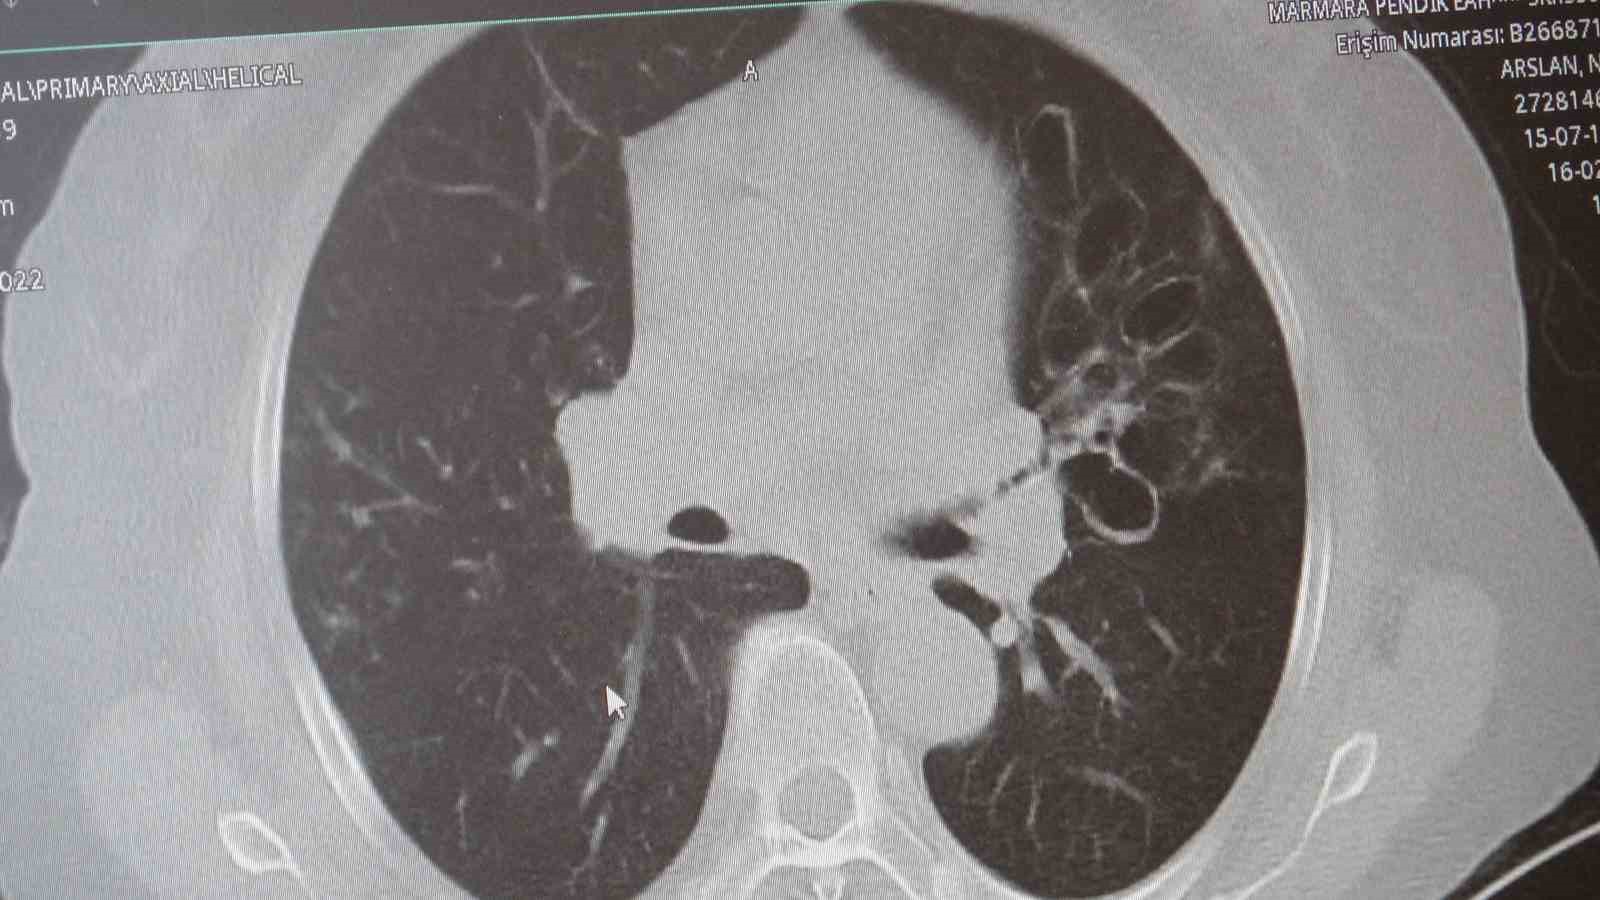

"KOAH toplumda sık görülen bir hastalıktır ve yaklaşık toplumda bunu yüzde 10 civarında görüyoruz. KOAH, zararlı maddelerin akciğeri parçalamasıyla oluşan bir rahatsızlık ve bunun da en önemli nedeni sigara. Vakaların aşağı yukarı yüzde 85’i sigara kullanımından kaynaklıdır. Bunun dışında hava kirliliği, iş yerlerinde kimyasal maddelere maruz kalma ve enfeksiyonlar da yine KOAH’ın nedenleri arasındadır. KOAH’ın önemi şu; bugün Dünya Sağlık Örgütü’nün (DSÖ) dünyada insanları öldüren hastalıklar listesinde ilk 10’da 4’üncü sırada yer alıyor. KOAH önlenebilir bir rahatsızlıktır; sigaranın bırakılmasıyla birlikte tamamen ortadan kalkacaktır."

KOAH’ın akciğer dokusunu tahrip eden bir hastalık olduğunu ve bu nedenle de hastaların enfeksiyona açık hale geldiğine dikkat çeken Karakurt, "Akciğer dokusunun tahrip olduğu her durumda hastaların enfeksiyona karşı eğilimi artar ve enfeksiyona yakalandıkları zaman bunun geçmesi güç olur. KOAH’lı hastalar zatürre geçirdikleri zaman öksürük ve balgam artışı gibi bir takım belirtiler gelişir. Ayrıca ateşin 38,5 derecenin üstüne çıkması, nefes darlığının artması, titremeyle birlikte ateşin yükselmesi ve bir takım bilinç bozukluğu gibi belirtiler hastanın zatürre olduğunu gösterebilir. Bu nedenle hastaların erkenden doktora başvurmaları önemlidir" şeklinde konuştu.